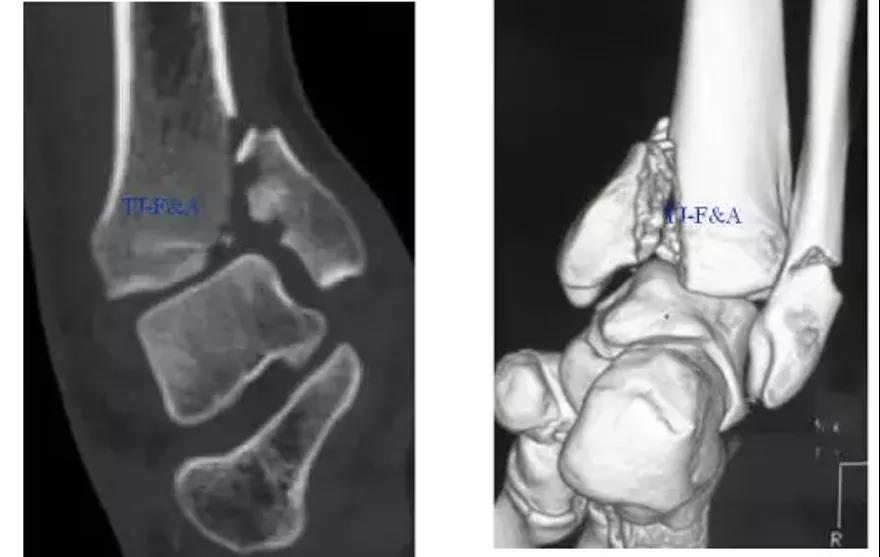

术前CT